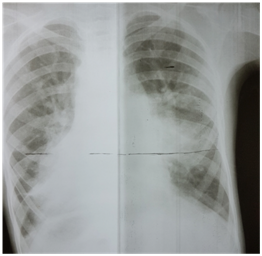

Because of the inherent risk of general anaesthesia (GA) in a patient with dysfunctional motility syndrome, we first intended to complete the catheter procedure with mild sedation and a local anaesthetic. However due to the non-cooperation on part of the patient, the procedure had to be accomplished under general anaesthesia. Right femoral vein and artery were cannulated used 5F radial sheath. During the procedure, we found the IVC to drain across the azyguous continuation into the right superior vena cava and then track through the dilated coronary sinus in the right atrium (Figure 2).

Figure 2 IVC draining across the azyguous continuation into the right superior vena cava and then follow through the dilated coronary sinus in the right atrium.